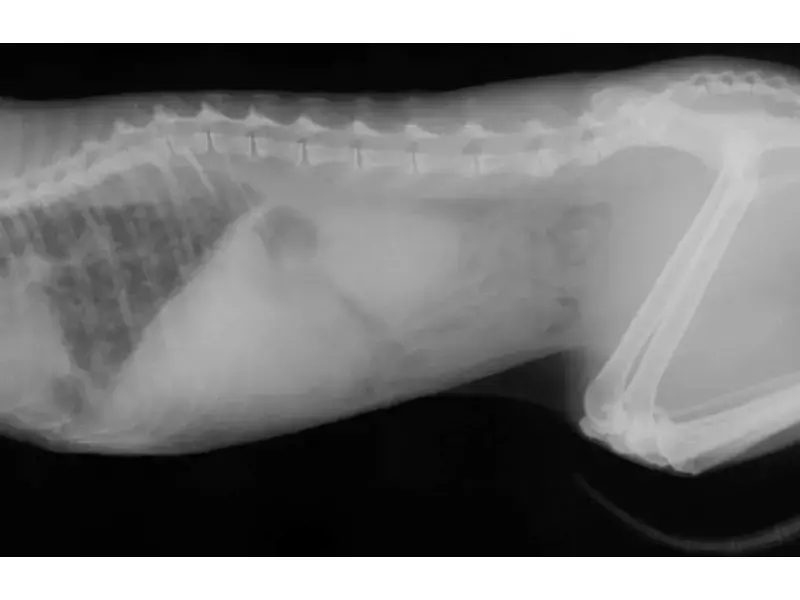

Предпоставките за развитие на белите дробове при котките могат да бъдат забелязани при профилактични прегледи при ветеринарен лекар, като се направи рентгенова снимка. Падането на налягането в системата прави горния дял на белия дроб по-отчетлив. Ако не се вземат подходящи мерки навреме, патологията само ще започне да прогресира. Впоследствие това ще доведе до подуване на съединителната тъкан, а по-късно, когато течността проникне още по-дълбоко, до запълване на алвеоларното пространство.

- рентгенова снимка на гръдния кош;